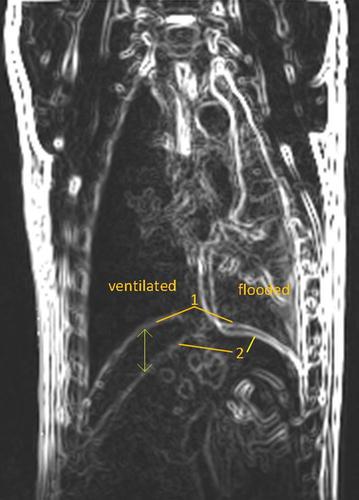

Double-lung ventilation increased the diaphragm movement in comparison with spontaneous breathing (17.8 ± 4.4 vs. 12.2 ± 3.4 mm, p = 0.014). Diaphragm movement on the flooded side during contralateral one-lung ventilation was significantly reduced compared to that during double-lung ventilation (3.9 ± 1.0 vs. 17.8 ± 4.4 mm, p = 0.041). By analysing the magnetic resonance images, the hemidiaphragm on the flooded side showed an average displacement of 4.2 mm, a maximum displacement of 15 mm close to the ventilated lung and no displacement at the lateral side.

与自主呼吸相比,双肺通气时膈肌运动增加(17.8±4.4 vs. 12.2±3.4 mm,p = 0.014)。与双肺通气期间相比,对侧单侧肺通气时灌注侧的膈肌运动显著减少(3.9±1.0 vs. 17.8±4.4 mm,p = 0.041)。通过分析磁共振图像,灌注侧半膈肌平均位移为4.2 mm,靠近通气肺处最大位移为15 mm,外侧无位移。